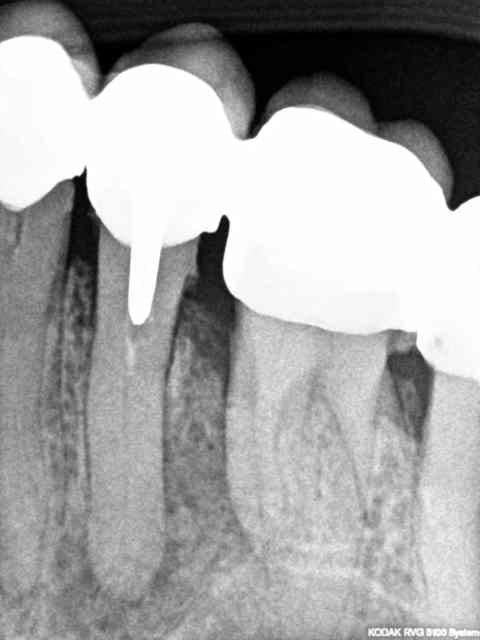

je viens de recevoir une patiente qui va se faire poser une prothèse de hanche dans 2 mois.

Dans un temps aussi court est-ce qu'il vous parait

possible de remettre en état sans pratiquer des extractions multiples, les endos sur 15 et 47 sont pratiquement inexistantes , bridge sur dents vivantes , tout est assymptomatique, 48?

désolée ... voici les radios

oups il manque celle là..